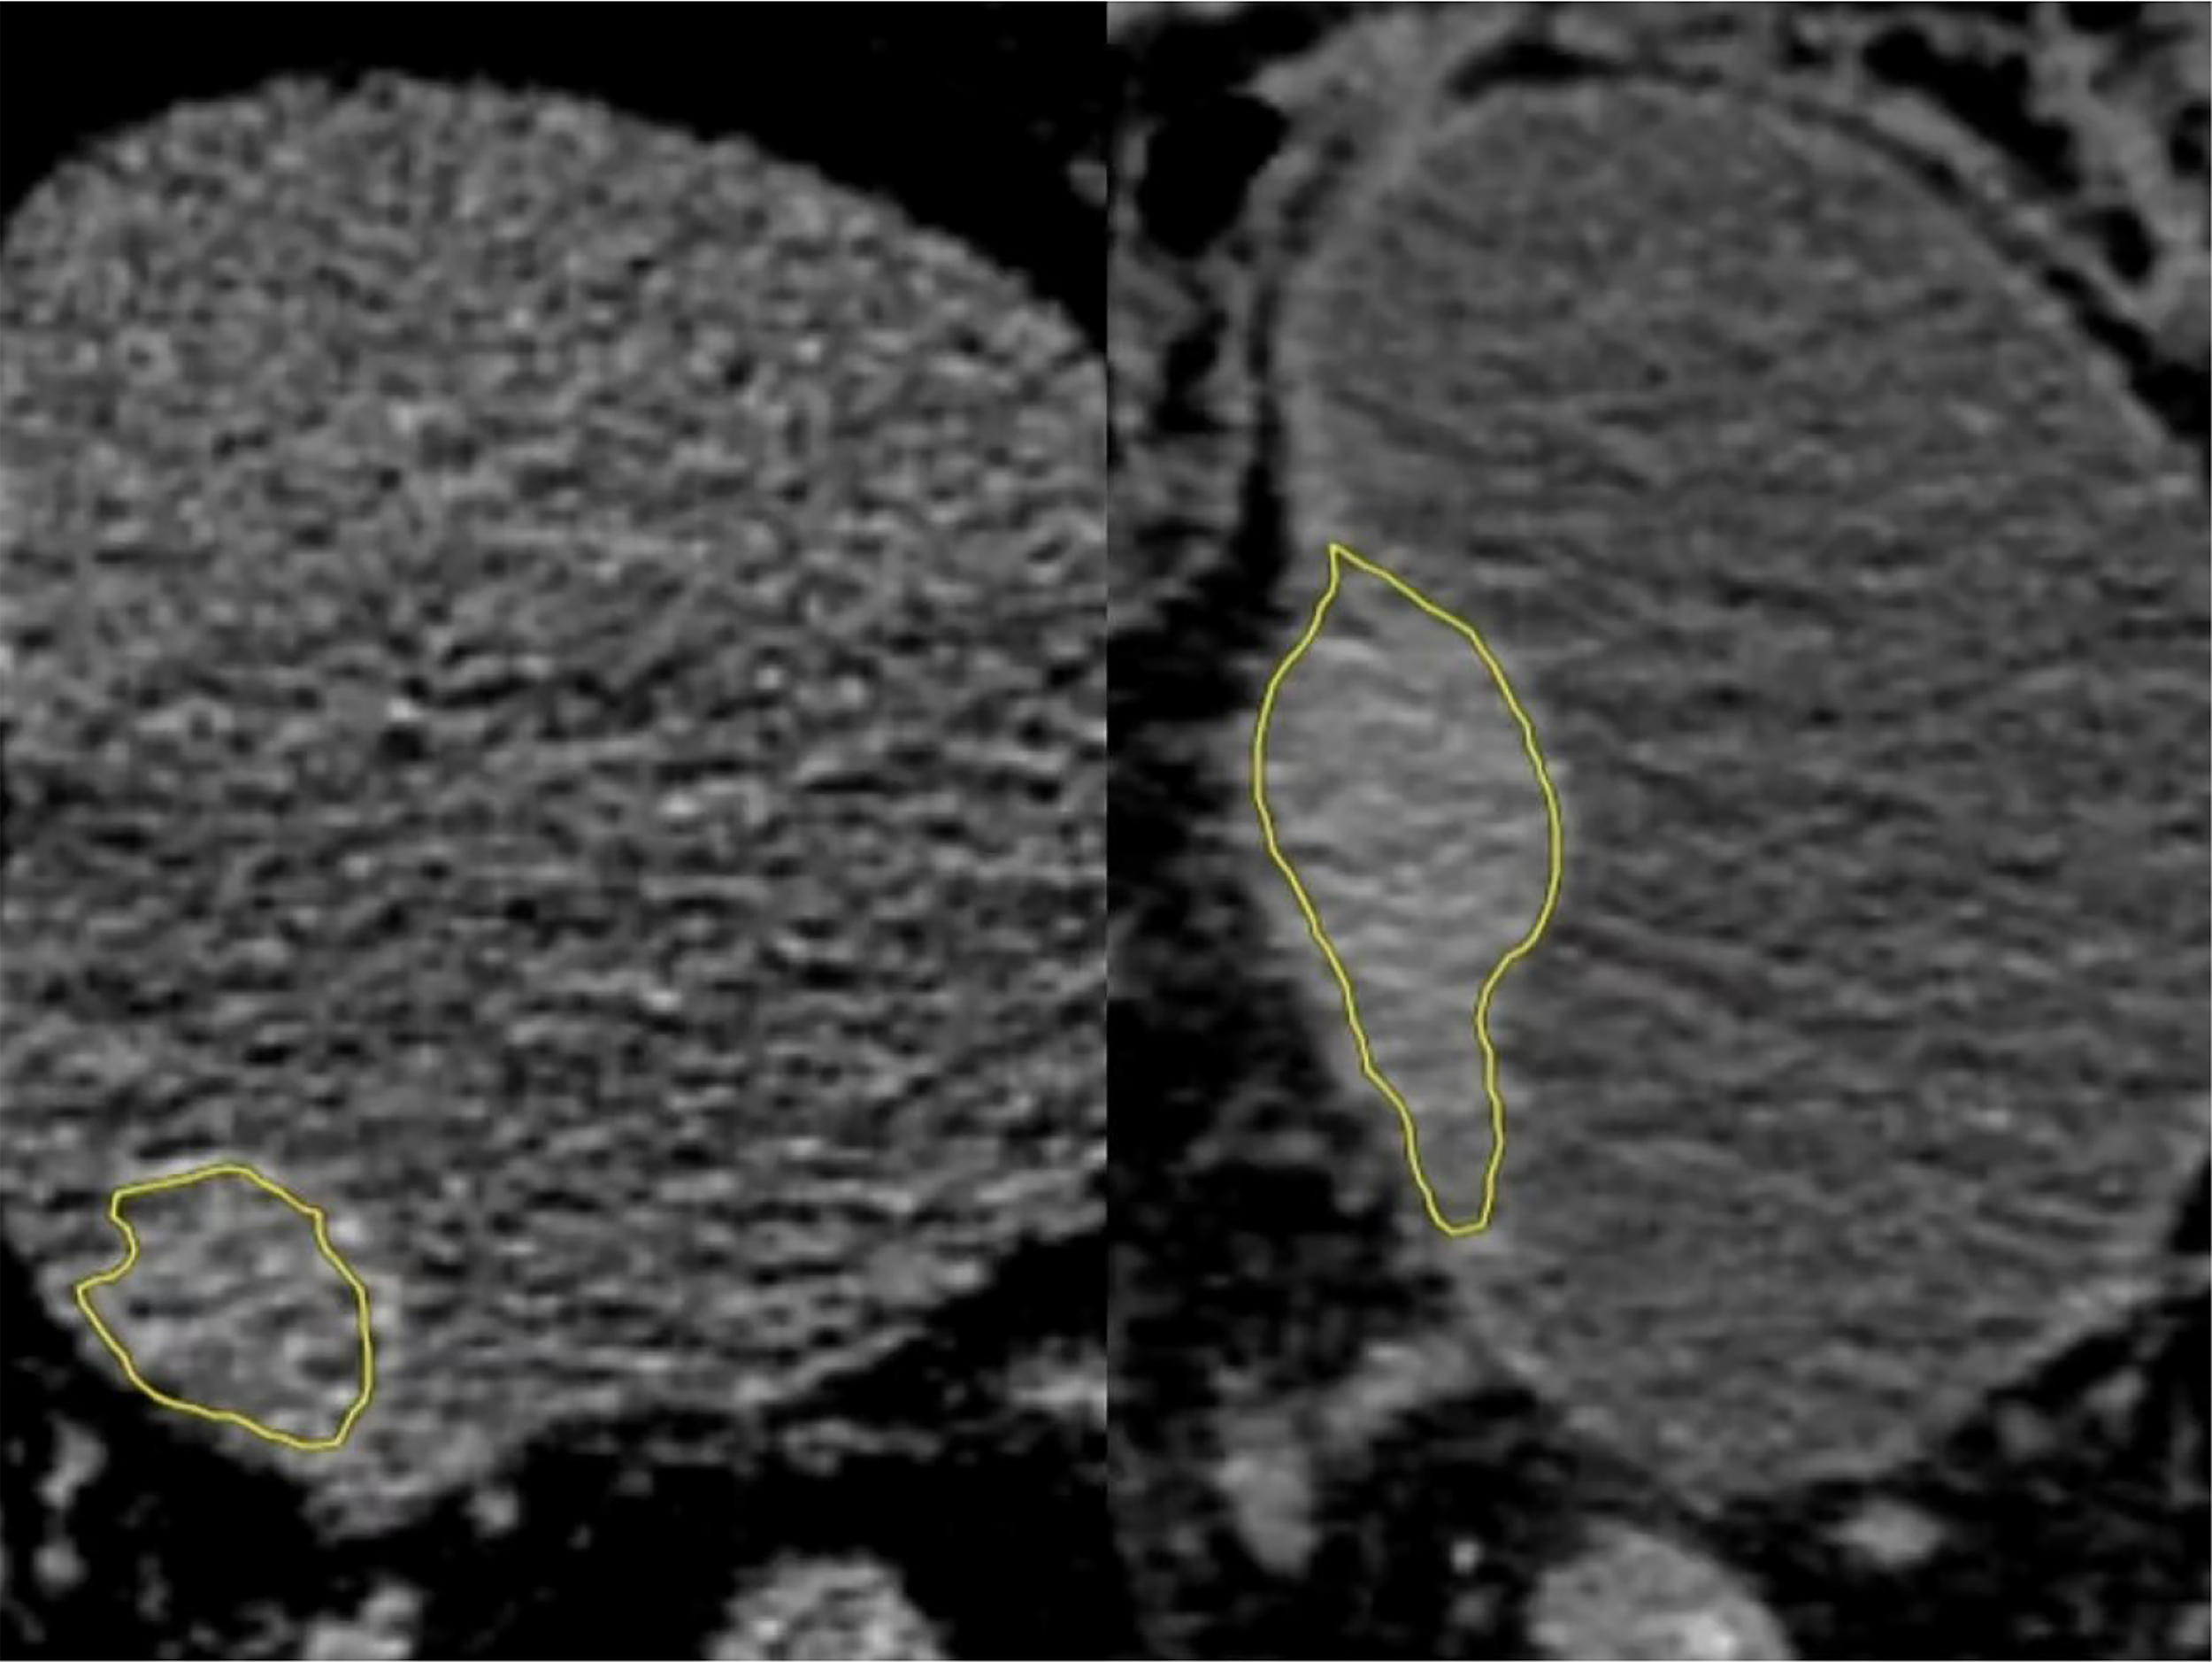

The CT image was segmented by an experienced radiologist (Reader A, with 5 years of experience in urogenital imaging). Areas of interest were outlined using DARWIN intelligent scientific research platform (19). One senior radiologist (Reader B, with 15 years of experience in urogenital imaging) reviewed all the region of interest (ROI) segmented by Reader A. If ROI was diverse, the senior radiologist determined the lesion boundary (Figures 1, 2).

Figure 2

Low-grade (left) and high-grade (right) regions of interest (ROIs). They were manually outlined in all layers of bladder cancer on the NE-CT images using image processing software (DARWIN intelligent scientific research platform), which were merged into a three-dimensional ROI diagram (yellow).